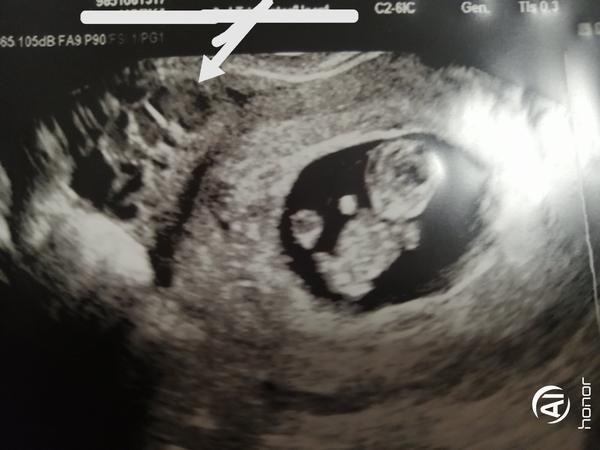

Prosím poraďte. Jsem dnes 9+5 TT. Ultrazvuk v pořádku doma ale na fotce jsme si všimli něčeho a nějak tapeme. Jestli jste se s tím některá nesetkala. Zda je tam druhé miminko nebo? Předem děkuji za odpověď. Ještě nemáme oznámené těhotenství proto anonymita. Viz foto- šipka.

Opravdu si myslis ze by druhe mimi takhle okatě nevideli? Je to vajecnik!

Druhé to určitě není, a největší pravděpodobností je to tlusté střevo

Plné tlusté střevo?

Vypadá to jako tlusté střevo a apendix 😁 ale při troše představivosti tam to miminko taky vidím 😂

Dnes jsem byla na utz a velmi podobně takto vypadalo žluté tělísko.